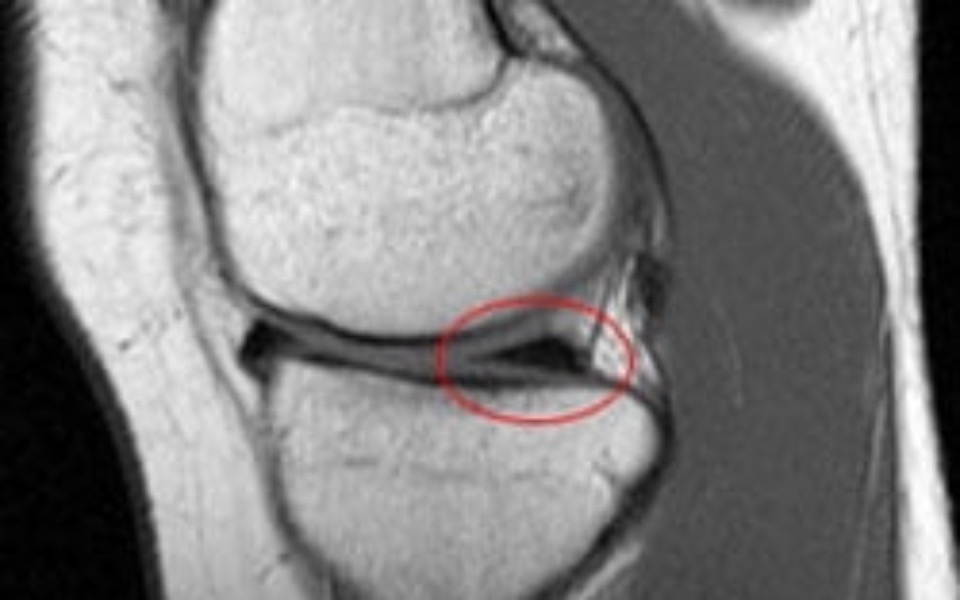

Witam zbieram na bardzo drogie lekki które będę musiał stosować po operacji kolana